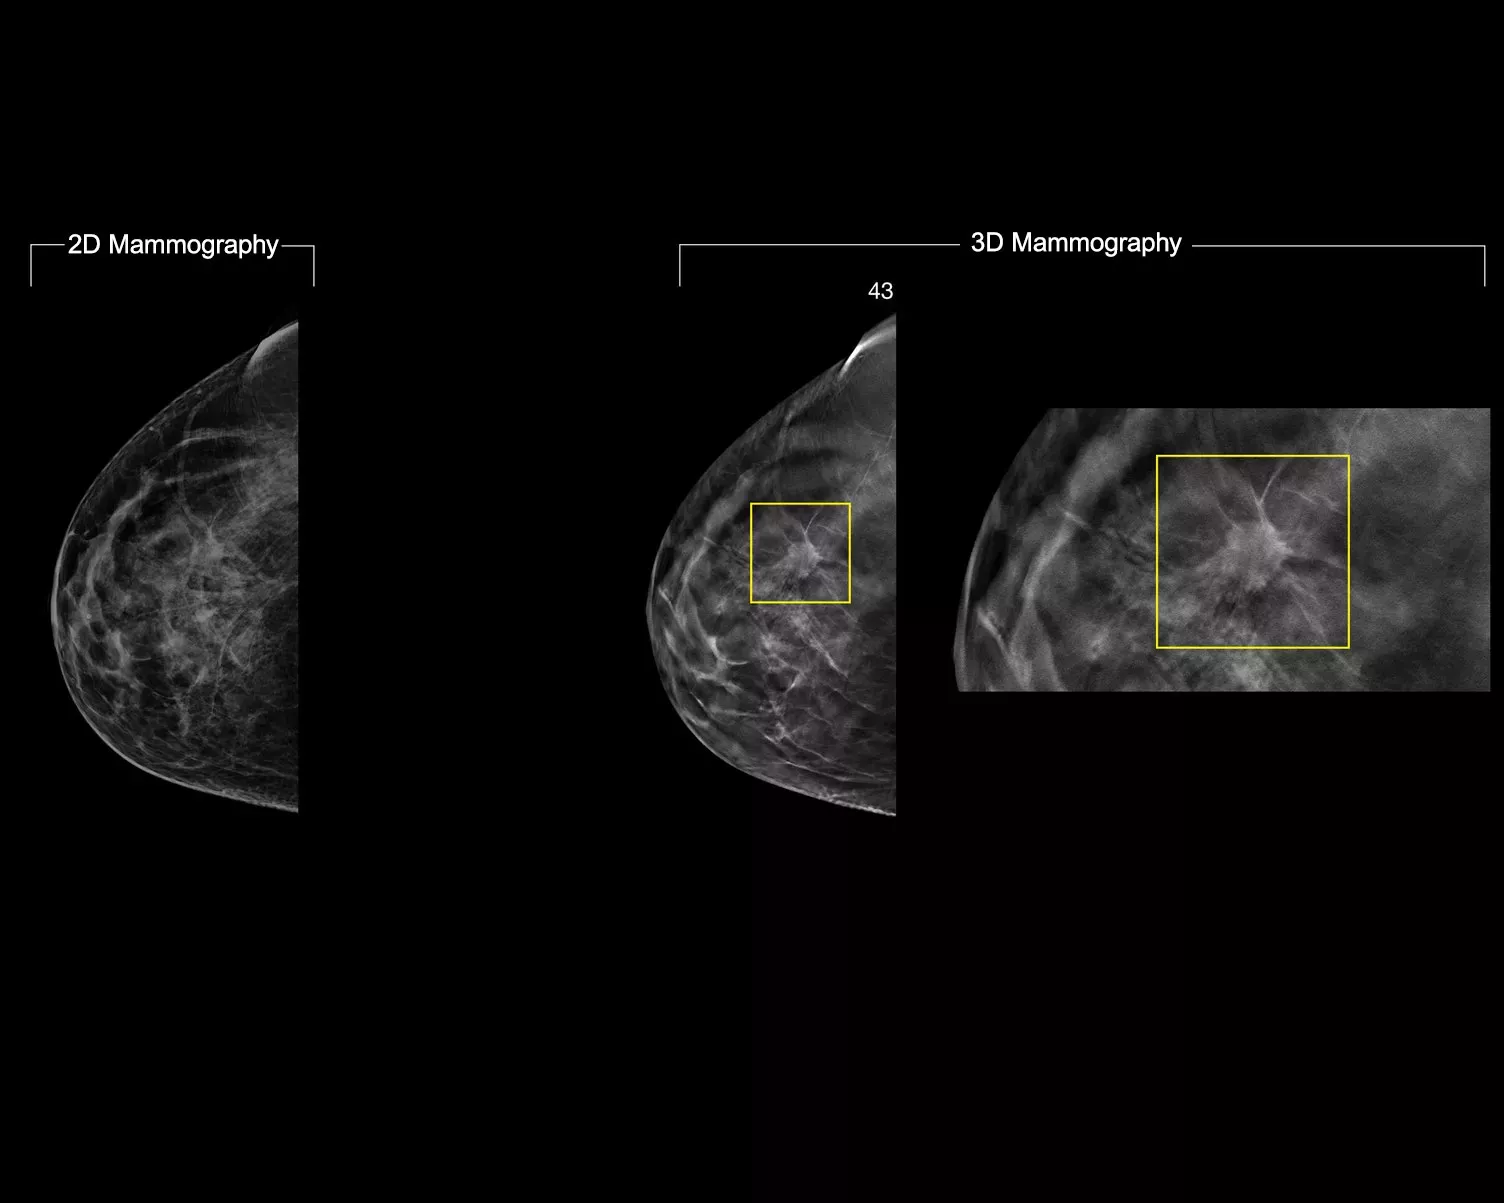

3DQuorum technology utilizes Genius AI™ powered analytics to uniquely reconstruct high-resolution 3D Mammography™ data to produce 6mm SmartSlices. It speeds up reading time by reducing the number of images to review, with no compromise in image quality, sensitivity or accuracy.2,3 With our newest innovation, you could reduce read times by an hour a day.2,3*

Genius AI analytics identifies regions of interest and preserves important features during the creation of SmartSlices.2 The 6mm with 3mm overlap of SmartSlices ensures no data loss and continuity in scrolling.4-6

When reading SmartSlices instead of 1mm slices, the number of 3D™ images to review is reduced by two-thirds.4-6 This saves an average of 1 hour per day in image interpretation time.3